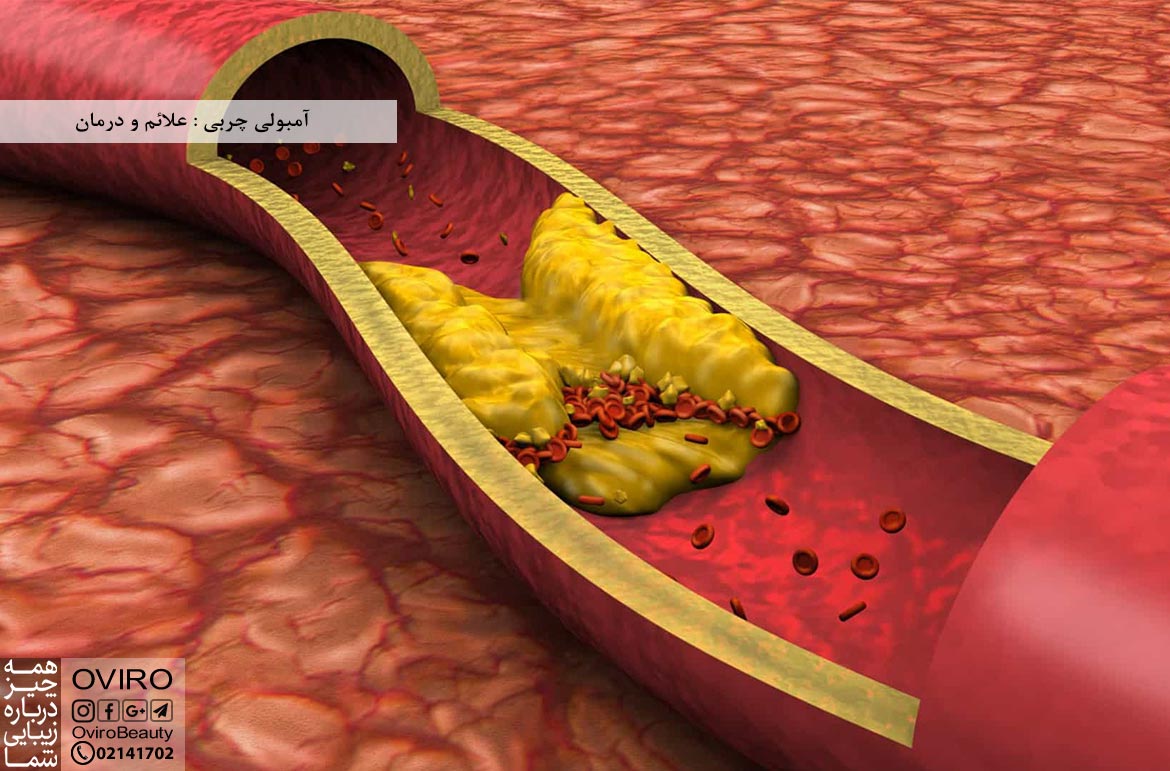

آمبولی چربی : علائم و درمان

زمانیکه چربی وارد رگ ها یا عروق شود آمبولی چربی رخ می دهد؛ علائم – علت – عوامل خطر –…